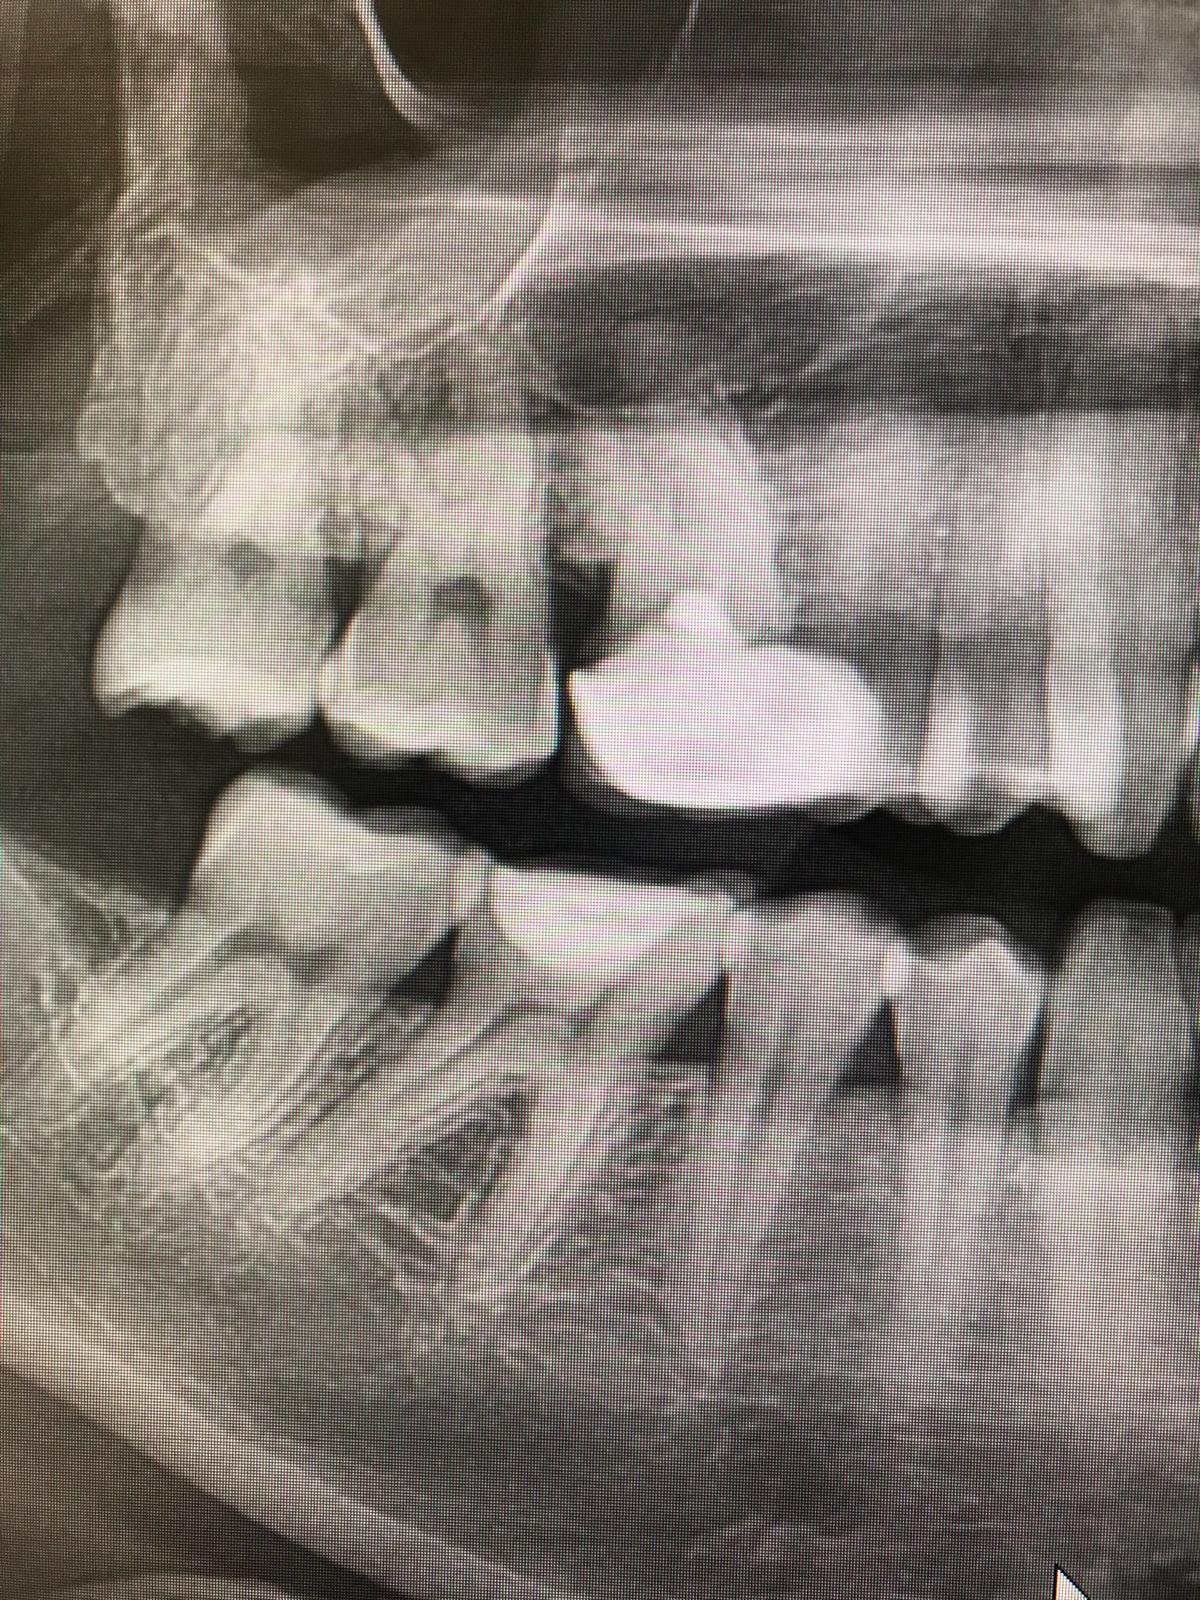

Riabilitazione post estrazione con impianto

Estrazione e Implantologia a Carico Immediato

Estrazione, Rigenerazione Ossea e Riabilitazione Implantare